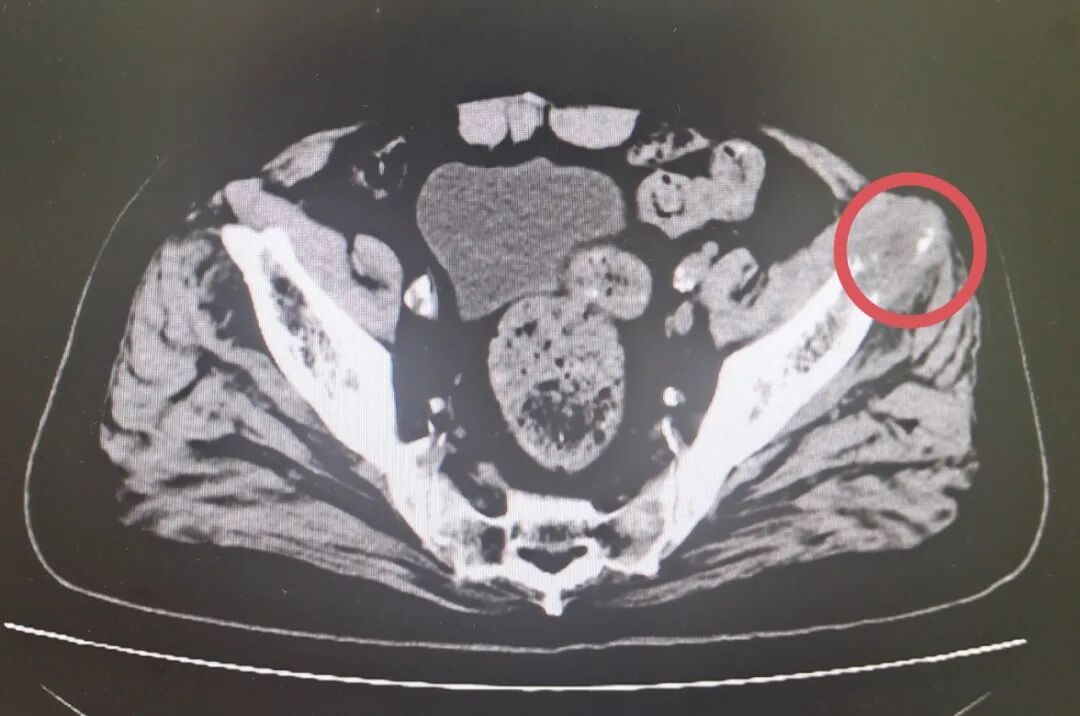

术前髋部CT影像

(红圈内为转移瘤病灶)